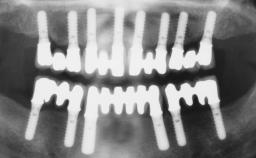

A 63-year-old female patient was referred to the University Medical Center in Groningen, Netherlands, for dental implant treatment. The patient had been edentulous in the upper jaw for 20 years. The remaining teeth in the lower jar had been removed two years before the consultation. The patient was wearing her first maxillary denture and her second mandibular denture; the latter was 1 year old at the time. The conventional upper denture had functioned satisfactorily for many years, but the patient complained about reduced stability and insufficient retention of her lower conventional denture. Her medical history revealed no significant findings. The intraoral examination revealed minor resorption of the maxillary alveolar process and extreme resorption of the mandibular alveolar process.

# of Implants 2

Defining Characteristics Fully edentulous lower jaw to be rehabilitated with two or more implants

Modality 2 interforaminal implants